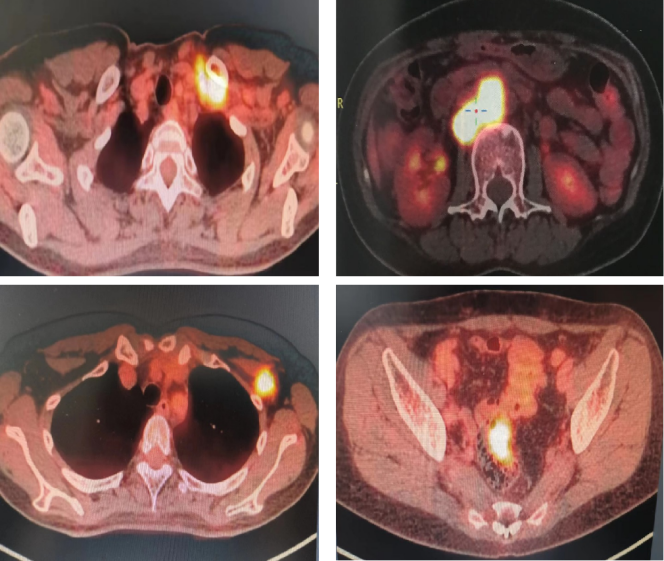

• 全身PET-CT(2022-02-11 vs 2021-09-23):PR。直乙结肠交界处病灶消失;左侧锁骨区、腹膜后淋巴结部分缩小,FDG代谢降低,部分消失;左侧腋窝肿大淋巴结消失。

10

直乙结肠交界处病灶消失,左侧锁骨区、腹膜后、左侧腋窝淋巴结明显缩小

• PET-CT(2022-07-21 vs 2022-02-11):CR。

①左侧锁骨区、左侧腋下、腹膜后未见肿大淋巴结,未见FDG代谢增高;

②直乙结肠交界处肠管管壁未见增厚,FDG代谢未见异常。

11

左侧锁骨区、左侧腋下、腹膜后未见肿大淋巴结,直乙结肠交界处肠管管壁未见增厚